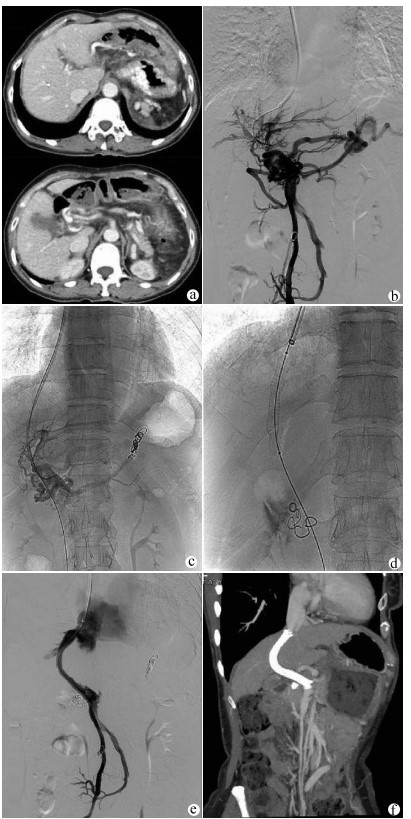

Value of transjugular intrahepatic portosystemic shunt in the prevention of esophageal variceal rebleeding in patients with portal vein thrombosis after splenectomy

•   Objective  To investigate the technical success rate and outcome of transjugular intrahepatic portosystemic shunt (TIPS) in preventing esophageal variceal rebleeding in patients with portal vein thrombosis (PVT) after splenectomy.  Methods  A retrospective analysis was performed for the clinical data of 46 patients with PVT after splenectomy who were admitted to Shandong Provincial Hospital from December 2009 to January 2017 and underwent TIPS to prevent esophageal variceal rebleeding. According to the success or failure of TIPS, the patients were divided into TIPS success group with 38 patients and TIPS failure group with 8 patients. The two groups were compared in terms of postoperative variceal rebleeding, stent dysfunction, hepatic encephalopathy (HE), and survival. The paired t-test was used for comparison of continuous data between two groups, and the chi-square test was used for comparison of categorical data between two groups. The Kaplan-Meier curve was used to analyze variceal rebleeding-free rate, stent patency rate, HE-free rate, and survival rate, and the log-rank test was used for comparison of cumulative rebleeding-free rate and cumulative survival rate.  Results  The technical success rate of TIPS was 82.6%. There were significant differences in 6-, 12-, and 24-month cumulative rebleeding-free rates between the TIPS success group and the TIPS failure group (94.3%/89.8%/89.8% vs 85.7%/85.7%/28.6%, χ2=4.563, P=0.033). In the TIPS success group, the 6-, 12-, and 24-month cumulative stent patency rates were 79.3%, 74.3%, and 69.0%, respectively, and the 6-, 12-, and 24-month cumulative HE-free rates after TIPS were 72.1%, 55.5%, and 55.5%, respectively. There were significant differences in 6-, 12-, and 24-month cumulative survival rates between the TIPS success group and the TIPS failure group (94.0%/94.0%/86.2% vs 71.4%/71.4%/71.4%, χ2=4.988, P=0.026).  Conclusion  TIPS is a safe and feasible method for preventing esophageal variceal rebleeding in patients with PVT after splenectomy, and TIPS combined with a percutaneous transhepatic approach may promote technical success.